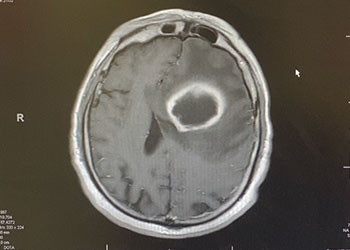

Image 1: Pre-treatment axial post contrast MRI. Because the lesion was sizeable, and causing much mass effect, and the diagnosis was unclear, and the patient was […]